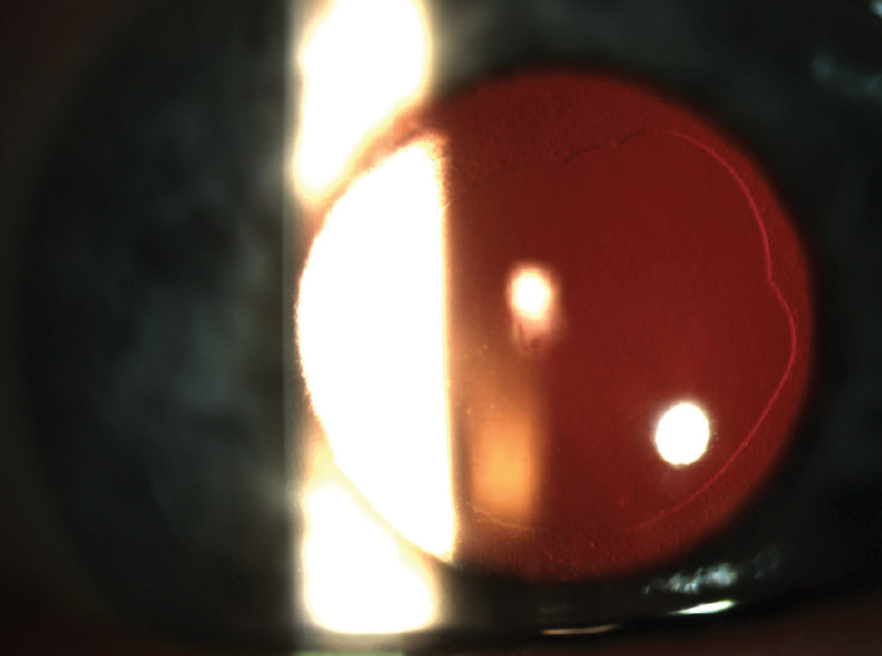

Figure 1. Postoperative corneal findings 1 day after DSO.

On the first postoperative day, UCVA was counting fingers at 5 ft OD. Slit-lamp examination showed a central descemetorhexis with overlying stromal and microcystic edema (Figure 1). The anterior chamber had 1+ cell, and the posterior chamber toric IOL was in place and centered. The patient’s postoperative drop regimen included prednisolone acetate 1%, ripasudil (Glanatec, Kowa), and sodium chloride 5%, each four times daily, and moxifloxacin three times daily (see Educated Decisions).